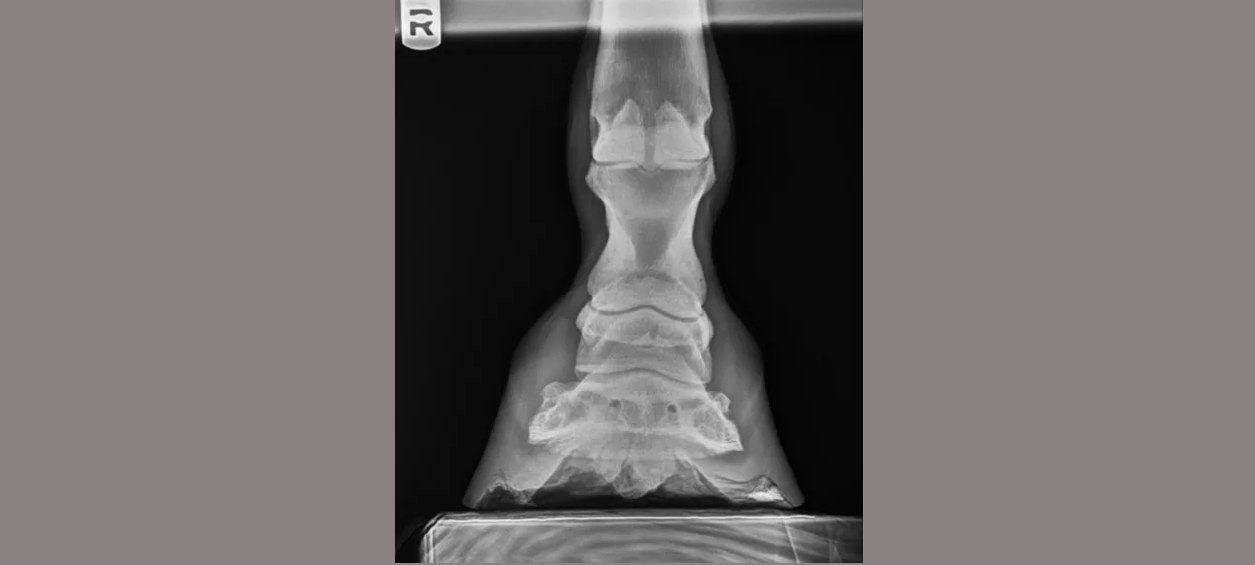

Abraham’s Equine Clinic is equipped with a state-of-the-art digital imaging system. This system provides us with crisp, high quality images of your horse’s skeletal system that are available for viewing instantly.

Digital imaging also allows us to easily manipulate the image on-screen to enhance images, highlight certain structures and magnify areas of interest. Digital images are much more easily taken, viewed, stored, shared and transferred than conventional or computed radiographs. We can easily email your radiographs to you or create a disc of your images for you to take with you after your visit. We have invested in this technology to provide our clients with the best quality radiographs that we can.